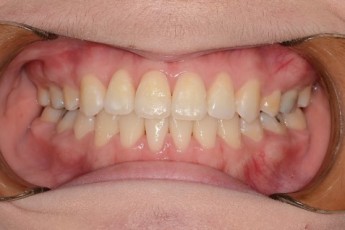

Before

After